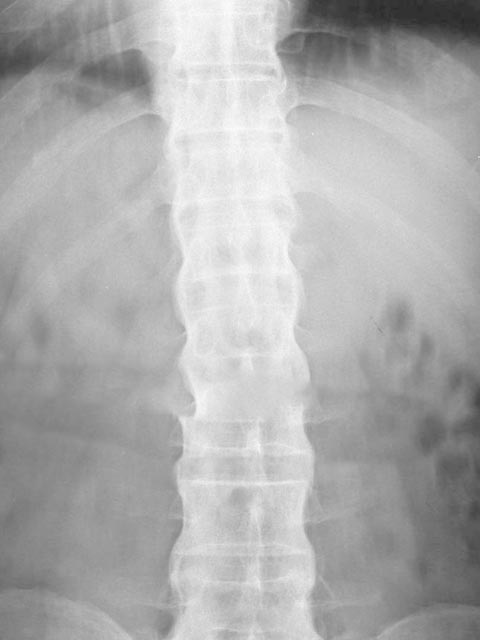

强直性脊柱炎的x线病变,最先起始于骶髂关节。随后,通常自下而上地由腰椎累及胸椎和颈椎,致使整个脊柱受到侵犯。晚期靠近椎体前缘和侧缘处,形成骨桥连接上下椎体,类似竹节状外观,故有“竹节状脊柱”之称。现在,由于医学发展,多数强直性脊柱炎患者,可得到早期诊断和早期治疗,竹节状脊柱的发生中已明显减少。